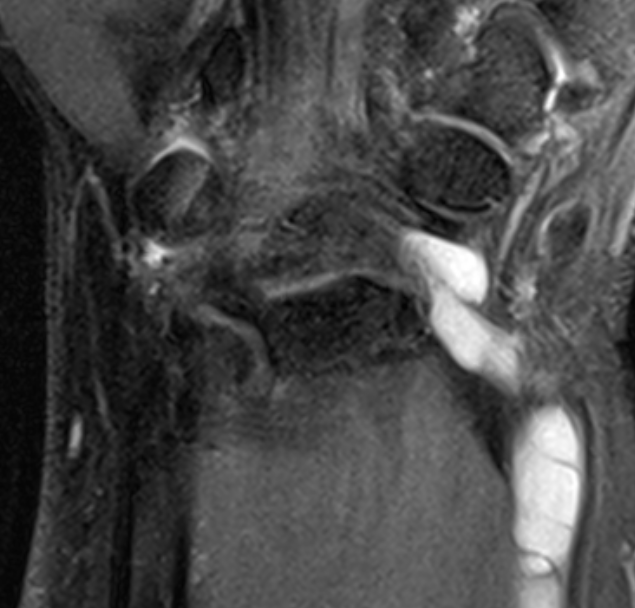

Dorsal ganglion

Dorsal ganglion arising from scapholunate joint

Dorsal ganglion arising from scapho-lunate joint